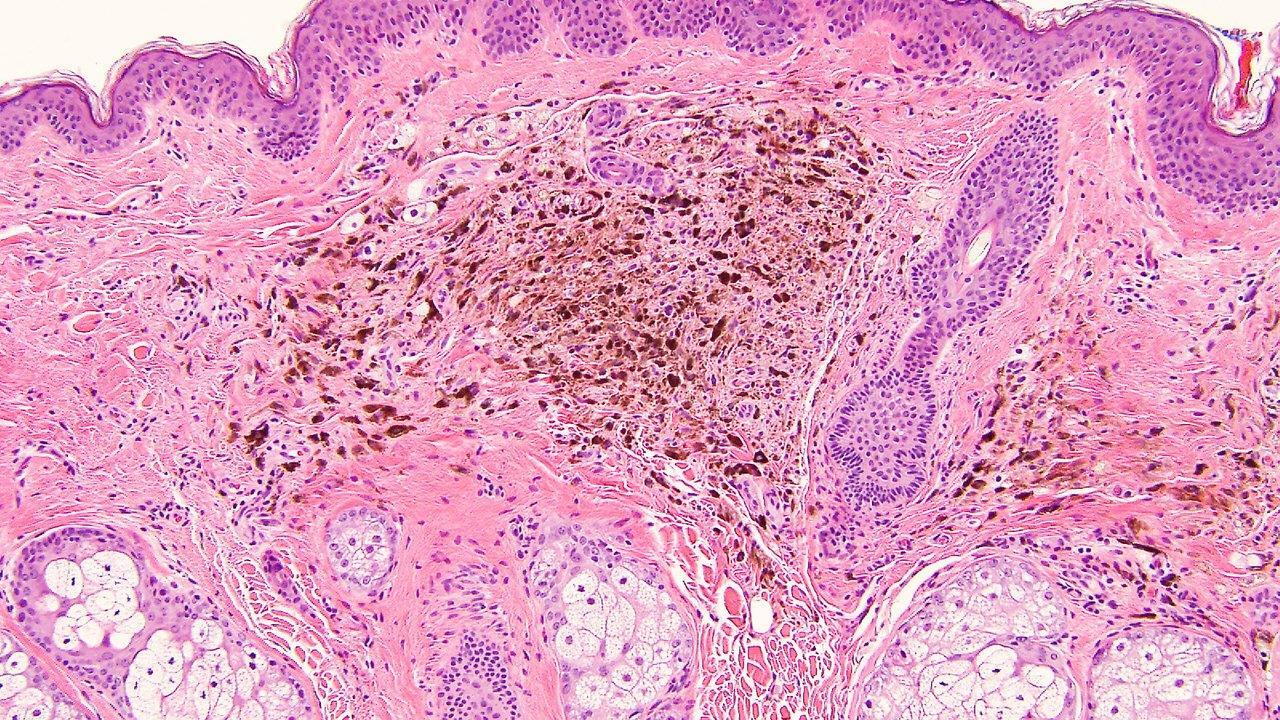

• Typical morphological findings: Epithelioid and naevoid components with associated lymphoid aggregates

• Pigmented epithelioid melanocytoma